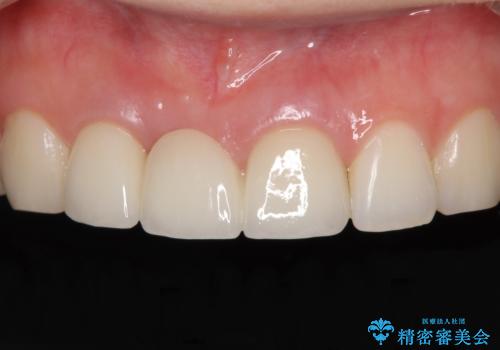

歯肉から血が 前歯のオールセラミックブリッジの再製作

- 他院で装着したばかりの前歯のブリッジが気に入らず、作り替えを希望して来院された患者様です。

前院では、土台の金属を除去することは不可能であると言われたとのことでした。金属の土台が残っているとセラミックにグレーの金属色が透けて見えてしまうため、拡大鏡やマイクロスコープを用いて丁寧に除去し、天然歯の色に近いファイバーコアを植立することとしました。

また、歯とクラウンの境目が合っていない部分が多く、歯肉からの出血が認められました。

金属色の透けた感じも歯肉からの出血もなくなり、自然な仕上がりの前歯となったので、患者様には大変満足していただきました。